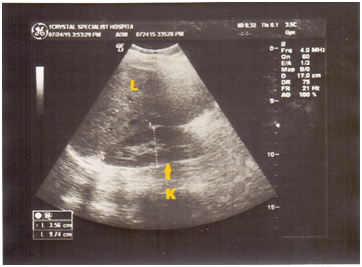

Sonographic confirmation of hypertrophied but ‘polar’ kidneys; similar to embedded renal cysts with predominantly low echogenicity and multiple sonopenic fluid spaces (Figure 1&2). A General Electric (GE) Pro-Logic 3 ultrasound machine (made in the USA) with a 3.5 MHz curvilinear transducer was used for scanning. There was no sonic evidence of malignant disease. Informed consent of patient was obtained and ethical approval was granted by CSH in line with the 1975 reviewed Helsinki Declaration on confidentiality and patient-rights. Prior to the diagnosis of hydronephrosis, fasting for 6 hours and dehydration test was made. Recent history review through oral discussion with patient and medical case-note revealed compulsive and excessive water intake about 5 years ago (Table 1).

Figure 1 Acute hydronephrosis of the RT kidney (K) with cystic-like corticomedullary differentiation, note isolated dilation of the renal pelvis.

Hydronephrosis caused by PUJ impairment formed approximately 38% of our previous study before this case report. Most of the patients who earlier came with symptoms to (CSH) were in the late teen-age group. On physical palpation subjects had tenderness and resistance in the lumber region, accounting for 88% of patients. A study9 in 2001 carried out pyeloplasty in 56 cases over a decade and concluded that the procedure is an excellent innovation for PUJ obstruction and produces clear urinary tract drainage. Although ill patients have undergone surgical procedure to alleviate functional tract obstruction8 we suggest treatment is made medical. Multiple dilated calyces (Figure 1), loss of corticomedullary differentiation, renal dysplasia and increased parenchymal echogenicity are all anatomical landmarks in-situ of the diseased kidneys.

Improved medication after a short period of time can lead to marked improvement in kidney tract dilation, if diagnosis by ultrasound is made early. Chronic renal failure rarely occurs11 however, persistent hydronephrosis presumably of many years can be improved and managed in line with the assertion of Tank et al.,12 Singer et al.,13 followed up stented patients; concluding medical management is of great value in the early detection of morbidity and other complications of hydronephrosis. Prolonged and sustained polyuria (diuresis >30/day) is usually a cause of reduced tubular fluid resorption and obstructed uropathy in some patients. This is similar to an earlier literature reporting by Drach.6 Multiple dilated calyces and loss of corticomedullary differentiation (Figure 1) and partial increased parenchymal echogenicity are all anatomical landmarks in-situ of the diseased kidneys.